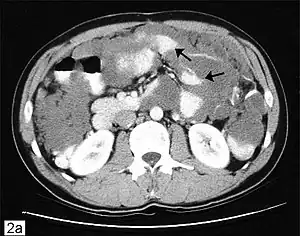

![]() Tomografie computerizată a abdomenului care arată un pseudomixom peritoneal cu multiple acumulări gelatinoase peritoneale (săgeată) | |